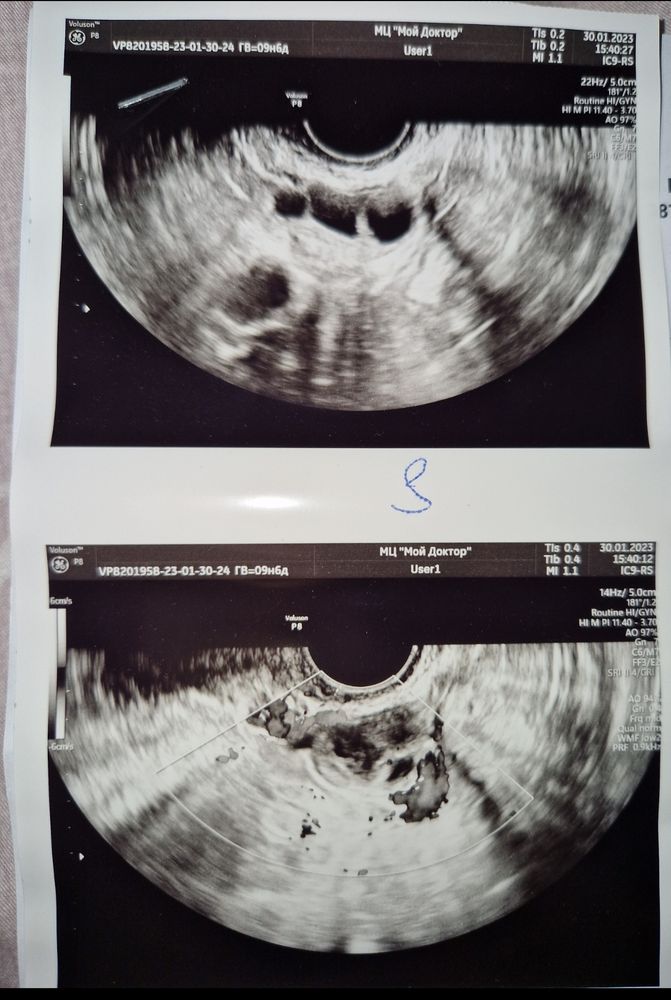

Аделина, фото с узи на 11 дц, может вы разберётесь, можно там путать или нет, я не могу понять там фолликулы, жт, или жидкость Изображение

Даняша, я не спец по УЗИ. Смотрю просто по Вашему заключению. Там написано (помимо наличия ЖТ) - жидкость в заднем своде, которая обычно появляется после овуляции

Даняша, на 11 только фолликулы

У вас на 11 день цикла был фолликул 16 мм и потом он исчез...на 14 его нет. Мне кажется она ошиблась,и тот который был 16 мм,как раз лопнул на 13 день и на 14 по УЗИ мы уже видим жёлтое тело и пропажу доминантного фоллика. И в заключении на УЗИ с 11 она пишет признаки овуляции, видимо фраза про желтое тело сперта с другого УЗИ,не могут так фолики и в левом менятся и так быстро расти за 3 дня.

А в правом яичнике фолликул уменьшился получается? А в левом, получается, один лопнул и от него жидкость , а др два дальше растут? Вот эти механизмы я не совсем понимаю.

Sabedoria, в левом сказали мог сдуться третий фолликул, жт в нем нет В правом доминантный лопнул, а два другие уменьшаются, деградирует или как там правильно называется